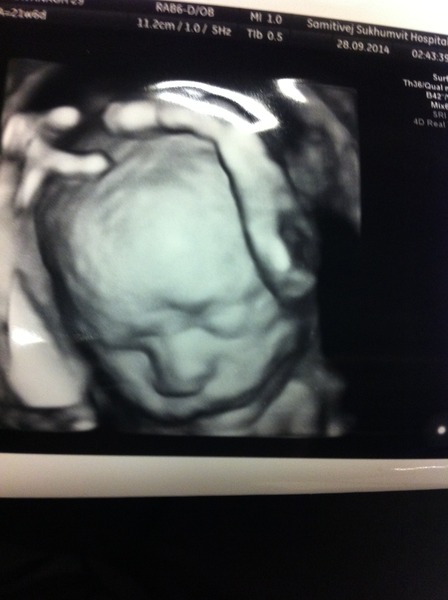

Hello ladies! I haven't been on in awhile but just thought I'd dip my toes back in. So happy to read about everyone's scans, kicks and see the pics! Here's my 3-D one from the 20-week scan (although actually was about 22 weeks at the time). We have confirmation - definitely a boy! He was all about rubbing his head, scratching his forehead and swallowing fluid getting his big mouth wide open - so amazing to see!! He's measuring all big (still within normal ranges though) and - heaves a sigh - head width is biggest of all. Ouch. My husband has a massive head, I knew this would happen. Apart from that, feeling pretty positive. Hope everyone else is feeling good, 23+4 here today! :) Also, I know this is a long shot but are there any other Feb ladies in Dublin (or anywhere in Ireland really?) And can whoever is organising the Fbook group PM me, I'd like to join!

Good luck to those with scans this week and Burmama, what a lovely pic!